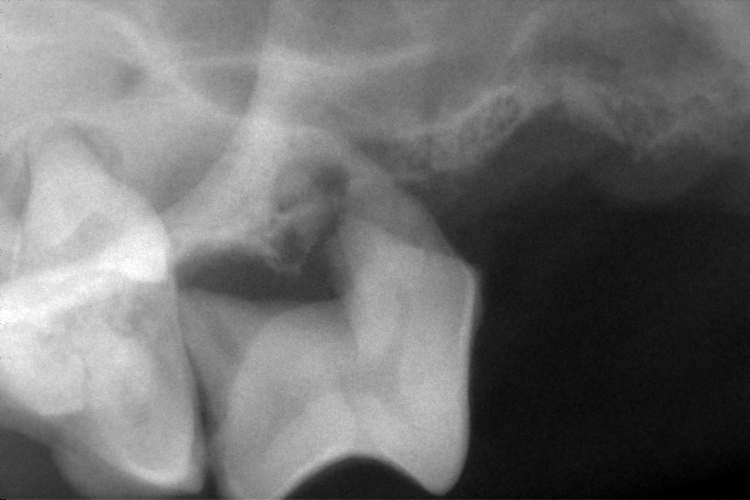

歯科レントゲン

右上顎第4前臼歯と右下顎第4前臼歯です。

黄色斜線部分の歯槽骨が溶け、黒く抜けているのが確認できます。